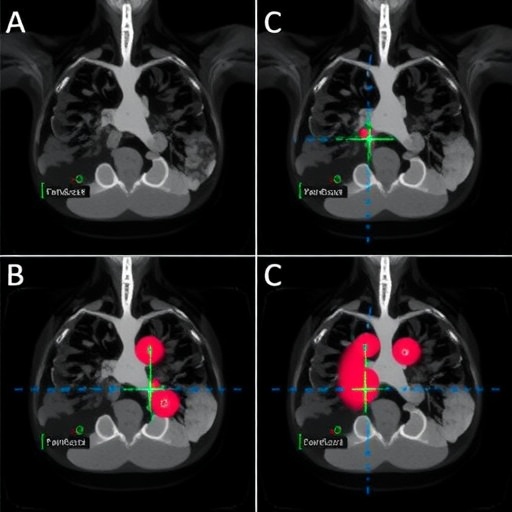

The foundation of the research rests on the premise that pre-processing is critical for enhancing image quality before it is fed into deep learning algorithms. Techniques such as noise reduction, contrast enhancement, and image normalization are fundamental to ensure that the data fed into these algorithms represent the breast tissue as faithfully as possible. This study meticulously outlines how these pre-processing methods mitigate common issues such as artifacts and disparities in image quality, which can significantly hinder diagnostic performance.

One of the standout findings from this study reveals that applying specific pre-processing techniques can yield striking improvements in segmentation accuracy. The researchers implemented various methods, examining their effects on state-of-the-art deep learning models. In doing so, they established a clear correlation between improved image quality and increases in segmentation performance. The significance of fine-tuning these pre-processing steps cannot be overstated, as they form the bridge between raw imaging data and valuable diagnostic insights.